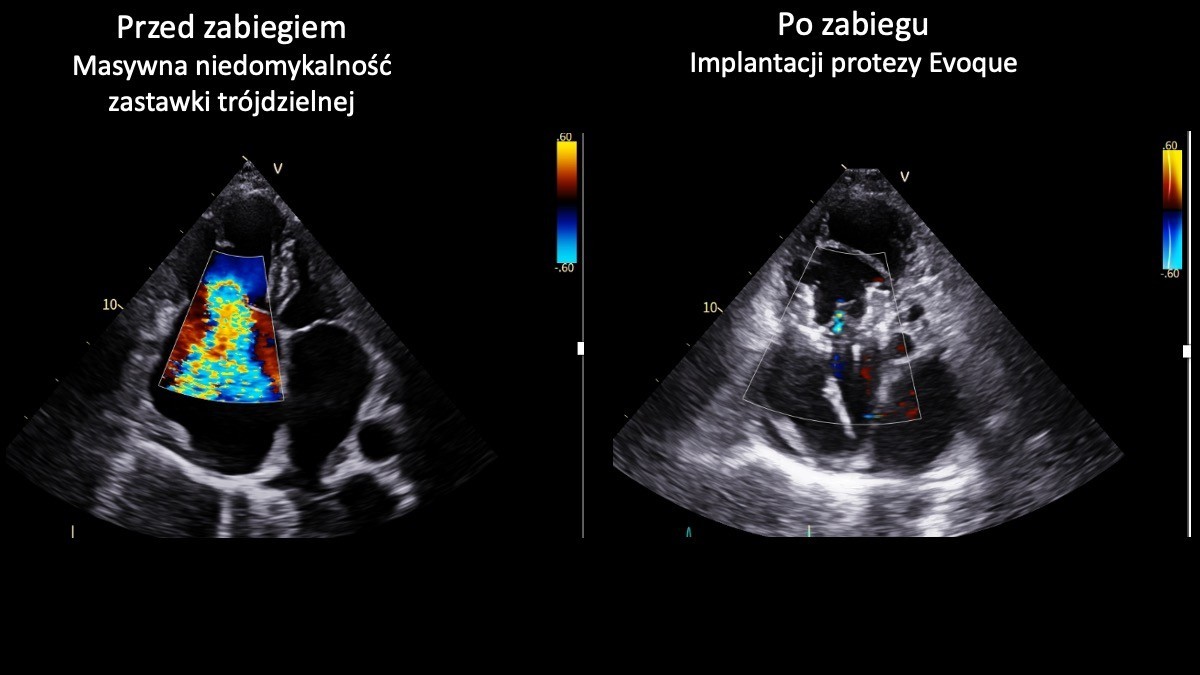

Przeprowadził dwa nowatorskie zabiegi przezcewnikowej implantacji zastawki trójdzielnej Evoque z wykorzystaniem wizualizacji 3D. Wykonał je zespół I Kliniki Kardiologii UCK GUMed, kierowanej przez prof. Marcina Gruchałę.

Zastawka trójdzielna odpowiada za prawidłowy przepływ krwi w prawej części serca. W przypadku jej niedomykalności krew cofa się, co prowadzi do przeciążenia serca i objawów takich jak duszność, szybkie męczenie się czy obrzęki kończyn dolnych. W zaawansowanej postaci schorzenie może skutkować niewydolnością serca i stanowić zagrożenie życia.

Obie przeprowadzone implantacje zakończyły się sukcesem. Dla pacjentów obciążonych bardzo wysokim ryzykiem operacyjnym i bez innych możliwości leczenia to obecnie jedyna realna szansa na skuteczną terapię – podkreśla prof. Marcin Fijałkowski.

Operacje wykonano u dwóch 80-letnich pacjentek. Dzięki zastosowaniu małoinwazyjnej metody przezcewnikowej możliwe było uniknięcie klasycznej operacji kardiochirurgicznej.

Pierwszy zabieg przeprowadzono z użyciem systemu echokardiograficznego GE HealthCare Vivid Pioneer, umożliwiającego obrazowanie serca w czasie rzeczywistym w technologii 3D. W drugim przypadku wykorzystano sondę wewnątrzsercową Philips VeriSight Pro 3D ICE, która zapewnia bardzo precyzyjną wizualizację struktur serca podczas procedury.

Jak przekonują lekarze w UCK zastosowanie tych technologii pozwoliło na dokładne przeprowadzenie implantacji i zaliczane jest do innowacyjnych rozwiązań w skali światowej. Obie pacjentki opuściły już szpital w stanie znacznej poprawy. Lekarze podkreślają, że tego typu procedury wyznaczają kierunek rozwoju leczenia zaawansowanych chorób serca i mogą w przyszłości stać się standardem terapii.